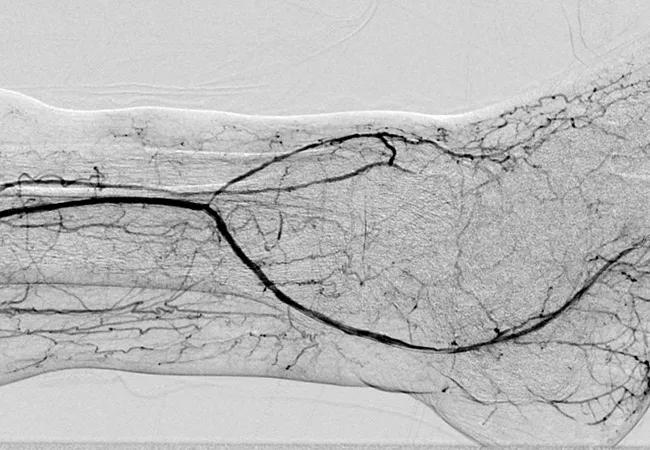

• A comprehensive analysis of a nationwide sample of nearly 650,000 hospitalized patients with CLI from 2003 to 2011. The paper, published in the Journal of the American College of Cardiology (and recapped here), outlined an abundance of trends in CLI management, including the fact that the decline in CLI surgeries is balanced by a rise in endovascular procedures for CLI.

• A retrospective analysis of CLI patients treated with endovascular therapy showing that most readmissions occur between 30 and 180 days after endovascular therapy for nonprocedural reasons and that unhealed wounds are independently associated with readmission. The study was published in the Journal of the American Heart Association.

• A retrospective study of CLI patients undergoing endovascular revascularization that focused on how time to wound healing impacts outcomes. The resulting paper in Annals of Vascular Surgery concluded that would healing should be achieved within three months to reduce risk of major amputation and within four months to reduce risk of major adverse limb events.